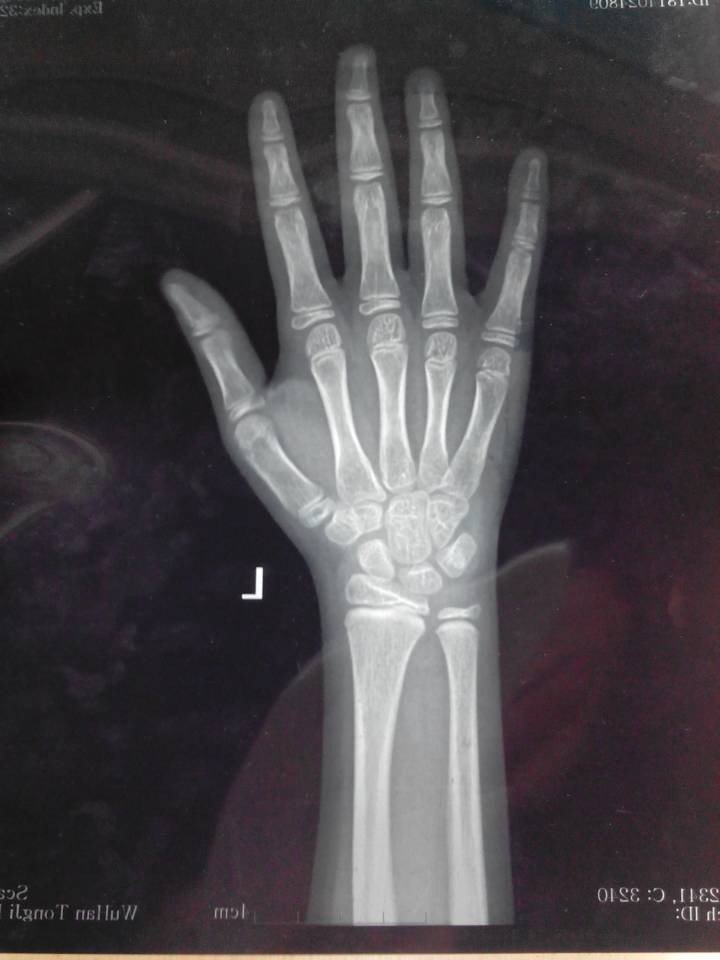

医生你好:我女儿今年8岁半,之前几年她经常喊膝关节痛疼,半年前开始出现乳房发育,半年来乳房小包时消 时长,最近发现没有消了且持续变大。孩子目前身高129.5cm,体重25kg,(孩子爸爸身高171cm,我的身高152cm),提供孩子4月11日刚拍的CT,不知道孩子的情况是否属于儿童性早熟?按目前的状态预测她的成年身高是多高呢?她这种情况需要治疗吗?如果需要治疗,要如何治疗呢?后期的治疗费用大概需要多少呢? 点击展开 匿名用户 2014-04-11 12:31 为您推荐: 其他回答 指导意见: 你好,这个如果孩子没有什么不适就没有问题的 ,.注意观察就可以了.必要时随时去医院进行检查 匿名用户 2014-04-11 15:26 相关问题 今天去给女儿做儿保医生检查出宝宝乳房有小块凝发育了可宝宝才1岁啊上网查了如果单纯乳房长大以后可能会 哺乳期乳房里面有几个小包做了彩超医生说没有事请问是什么原因,而且不痛不痒的 你好医生,我现在乳房一碰就疼是怎么回事啊?

时长,最近发现没有消了且持续变大。孩子目前身高129.5cm,体重25kg,(孩子爸爸身高171cm,我的身高152cm),提供孩子4月11日刚拍的CT,不知道孩子的情况是否属于儿童性早熟?按目前的状态预测她的成年身高是多高呢?她这种情况需要治疗吗?如果需要治疗,要如何治疗呢?后期的治疗费用大概需要多少呢?